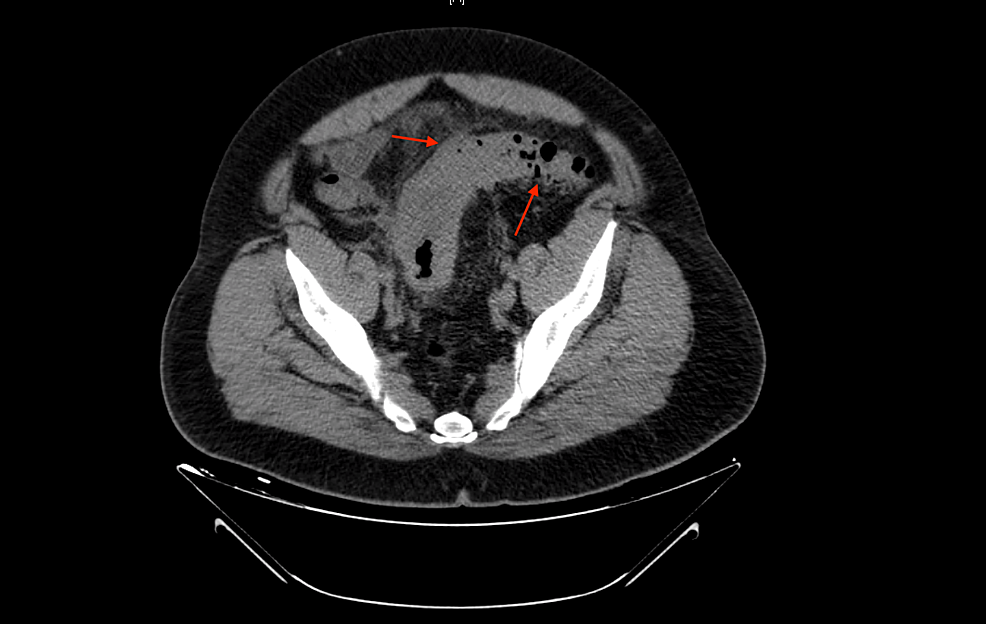

From litfl.com

Abdominal CT diverticulitis • LITFL • Radiology Library Lettuce In Diverticulitis Fiber is your friend when it comes to good digestive health. Modifying your diet is an excellent first step to taking control of diverticulosis and diverticulitis. Foods to consider avoiding include red meat and. That can cause symptoms such as. Diverticulosis happens when small pouches (diverticula). Increasing your dietary fiber intake with foods like lettuce may reduce your symptoms of. Lettuce In Diverticulitis.

Abdominal CT diverticulitis • LITFL • Radiology Library Lettuce In Diverticulitis Increasing your dietary fiber intake with foods like lettuce may reduce your symptoms of diverticulosis, as well as prevent complications including diverticulitis, which is an. Foods to consider avoiding include red meat and. Fiber is your friend when it comes to good digestive health. That can cause symptoms such as. These include high fiber foods and probiotics. Certain foods may. Lettuce In Diverticulitis.